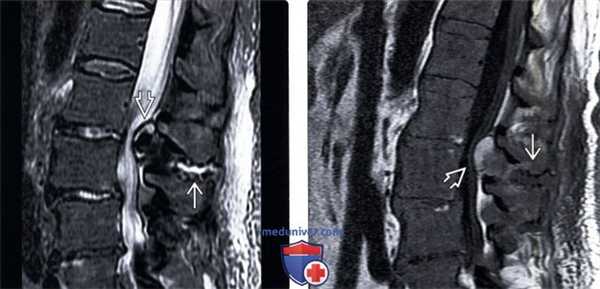

(Слева) Т2-ВИ, аксиальный срез: кистозные дегенеративные изменения при болезни Бааструпа в виде фокусов усиления сигнала вдоль остистых отростков и в прилежащих мягких тканях. Также видны признаки выраженного двустороннего дегенеративного поражения дугоотростчатых суставов с выпотом в их полость.

(Справа) STIR МР-И, сагиттальная проекция: признаки формирования бурсы в области межостистого промежутка L4-L5, выглядящей как линейный участок усиления сигнала. Признаков изменения сигнала прилежащих участков костного мозга нет. Обратите внимание на спондилолистез II степени на уровне L4-L5.

(Слева) Т1-ВИ, аксиальная проекция: выраженный центральный стеноз спинномозгового канала, связанный с диффузным пролабированием фиброзного кольца диска в переднем отделе канала и дегенеративной гипертрофической артропатией дугоотростчатых суставов сзади, которые вкупе приводят к сдавлению дурального мешка.

(Справа) Т2-ВИ, аксиальный срез: тяжелый центральный стеноз спинномозгового канала на фоне выраженной дегенеративной артропатии дугоотростчатых суставов. Дуральный мешок приобрел форму трилистника. (Слева) Т2-ВИ, сагиттальная проекция: тяжелый центральный стеноз спинномозгового канала на уровне L4-L5, обусловленный выраженным утолщением желтой связки. Гиперинтенсивность сигнала в области межостистой связки свидетельствует о ее дегенерации, которая также носит название болезни Бааструпа или межостистого бурсита.

(Справа) Т2-ВИ, сагиттальная проекция: признаки стеноза спинномозгового канала на уровне L3-L4 с пролабированием межпозвонкового диска и утолщением связочных структур. Обратите внимание на змеевидные низкоинтенсивные линии в краниальном отделе дурального мешка, представляющие собой «сгофрированные» корешки спинного мозга.